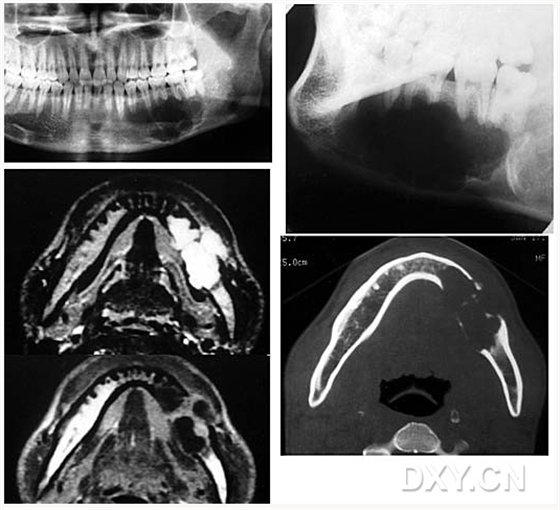

骨肉瘤